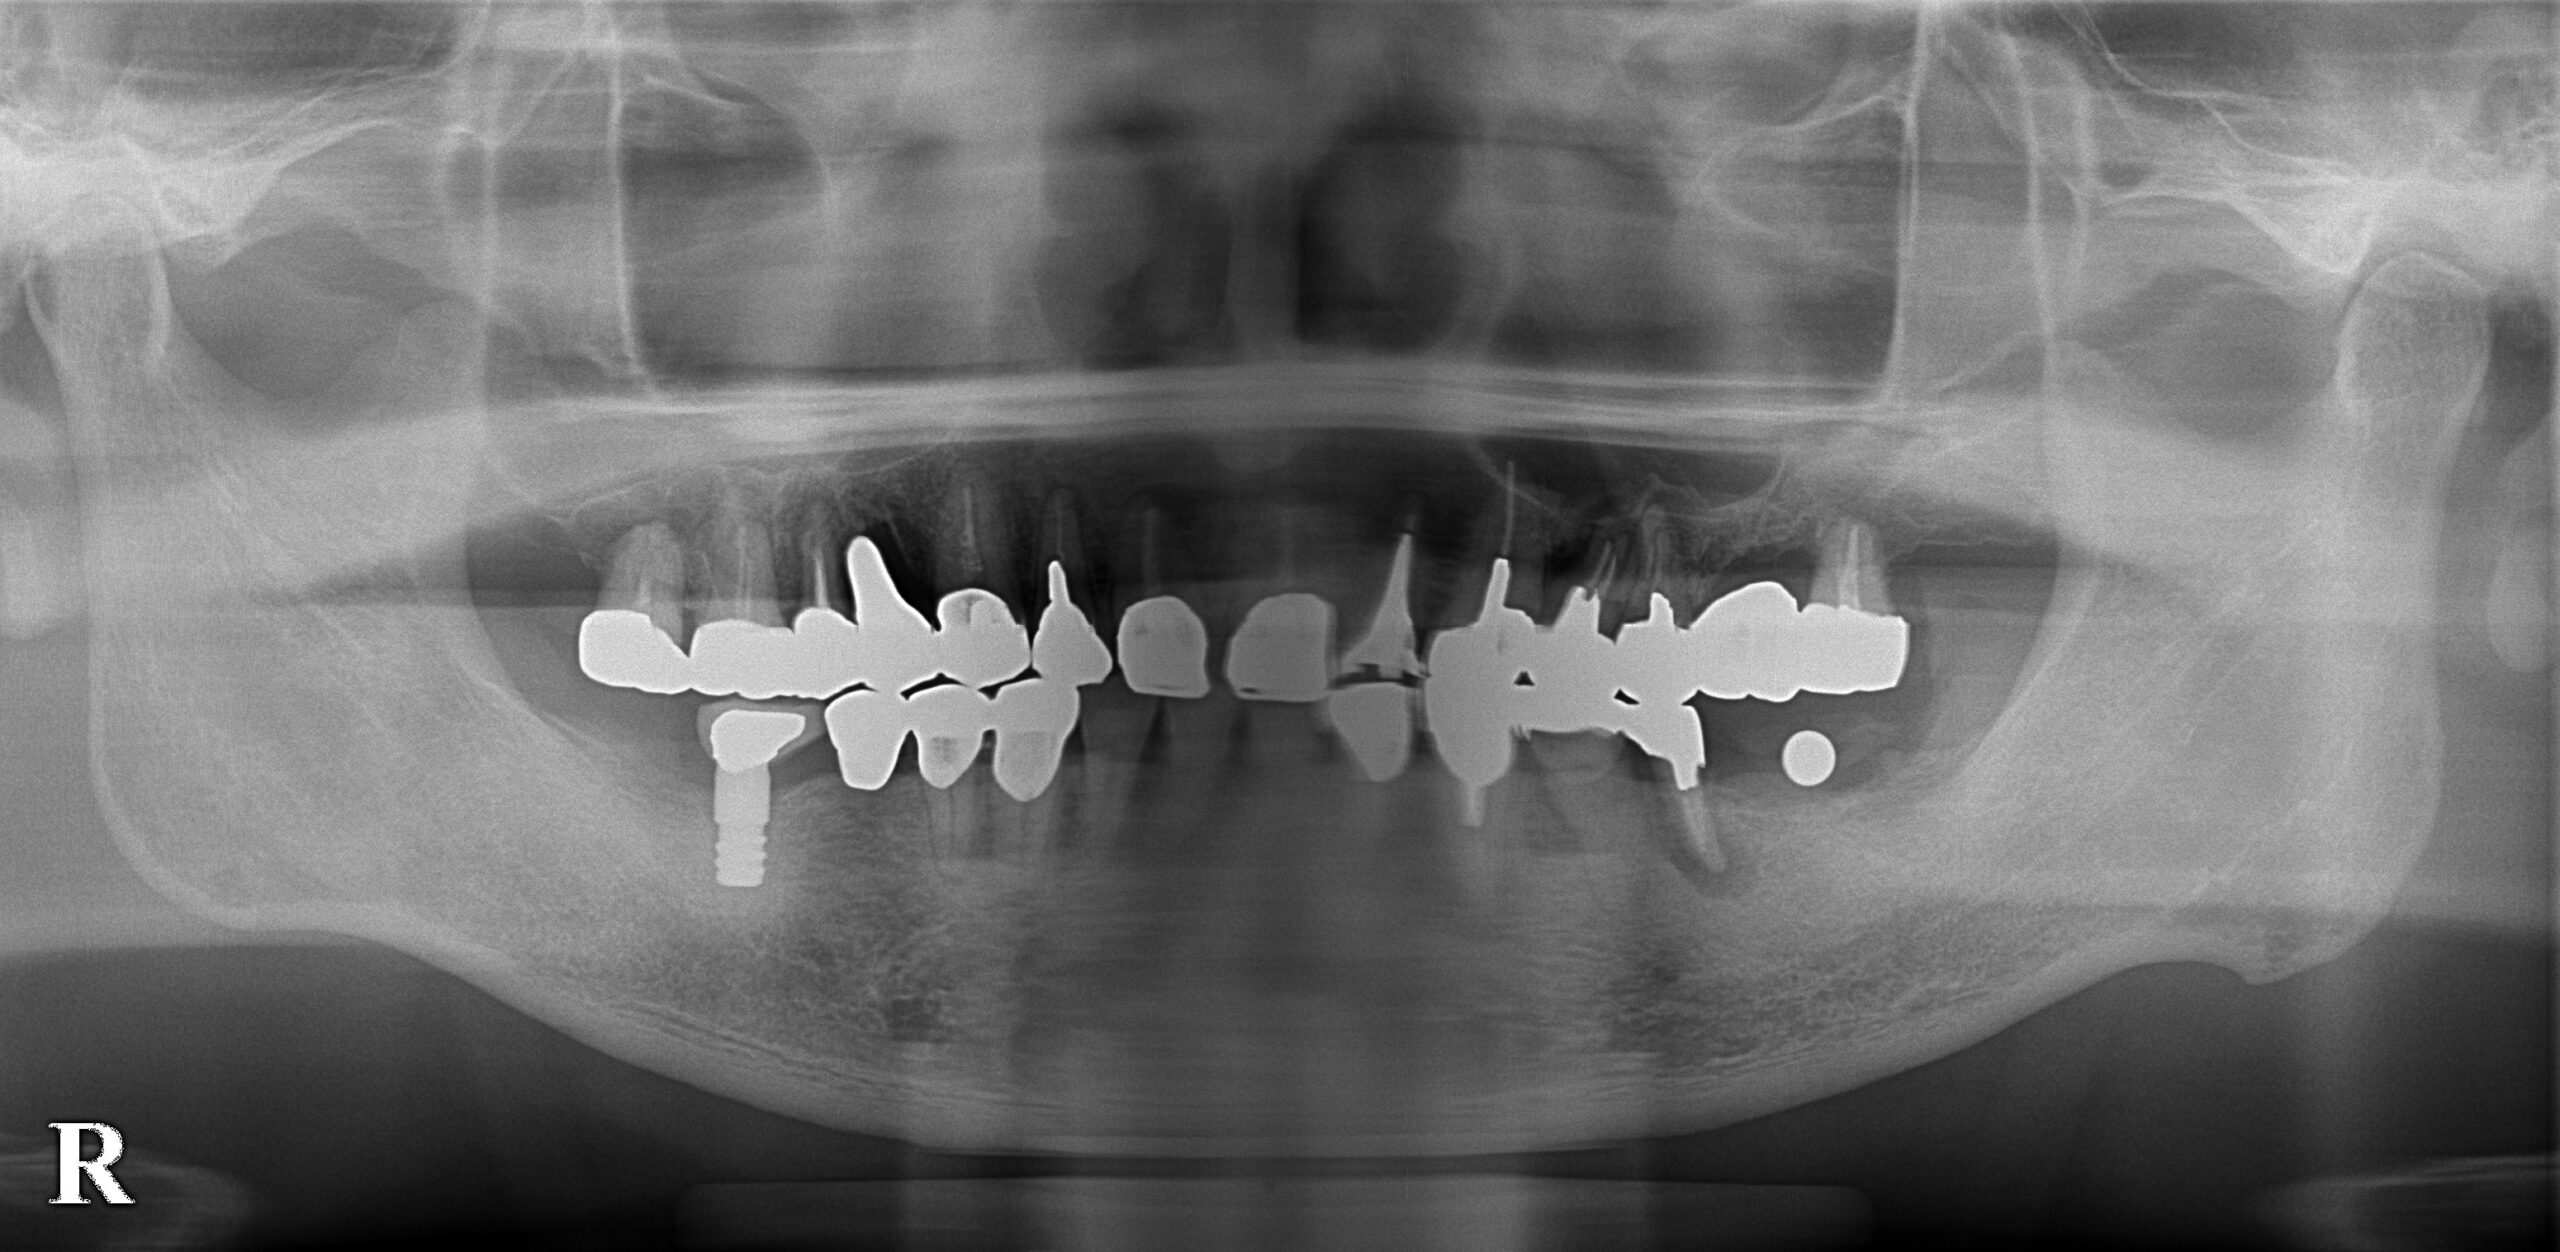

当院では、歯科用CTや口腔内カメラなどを使用して、削る量を最小限に抑える取り組みを行っています。

また、歯の健康な部分を大切に残すことで、歯そのものの強さを守り、再治療のリスクを減らしていきます。

当院では、治療を始める前に3Dレントゲンや口腔内写真・過去の症例データをもとに、現在の状態や治療内容を分かりやすくにご説明します。

また、症例データを用いて視覚的にも分かりやすく内容を伝えることで、患者様にご納得いただいた上で治療を進めています。

検査

お口の中の状態を確認し、必要に応じてレントゲン撮影などの検査を行います。症状の原因を把握し、 適した治療につなげるためにしっかり確認します。

歯の移動を早めるベッグ法を取り入れた矯正治療から日本人の歯に合わせた国産のインプラントを使用しており、精密な治療を受けることができます。

また、歯科用CTや3Dプリンターなどの最新設備に加えて、衛生管理を徹底するために院内感染防止対策機器などの医療設備もご用意しております。

3Dレントゲンや痛みを感じさせない電動麻酔器も導入していますので、東松山の患者様は安心して受診できます。